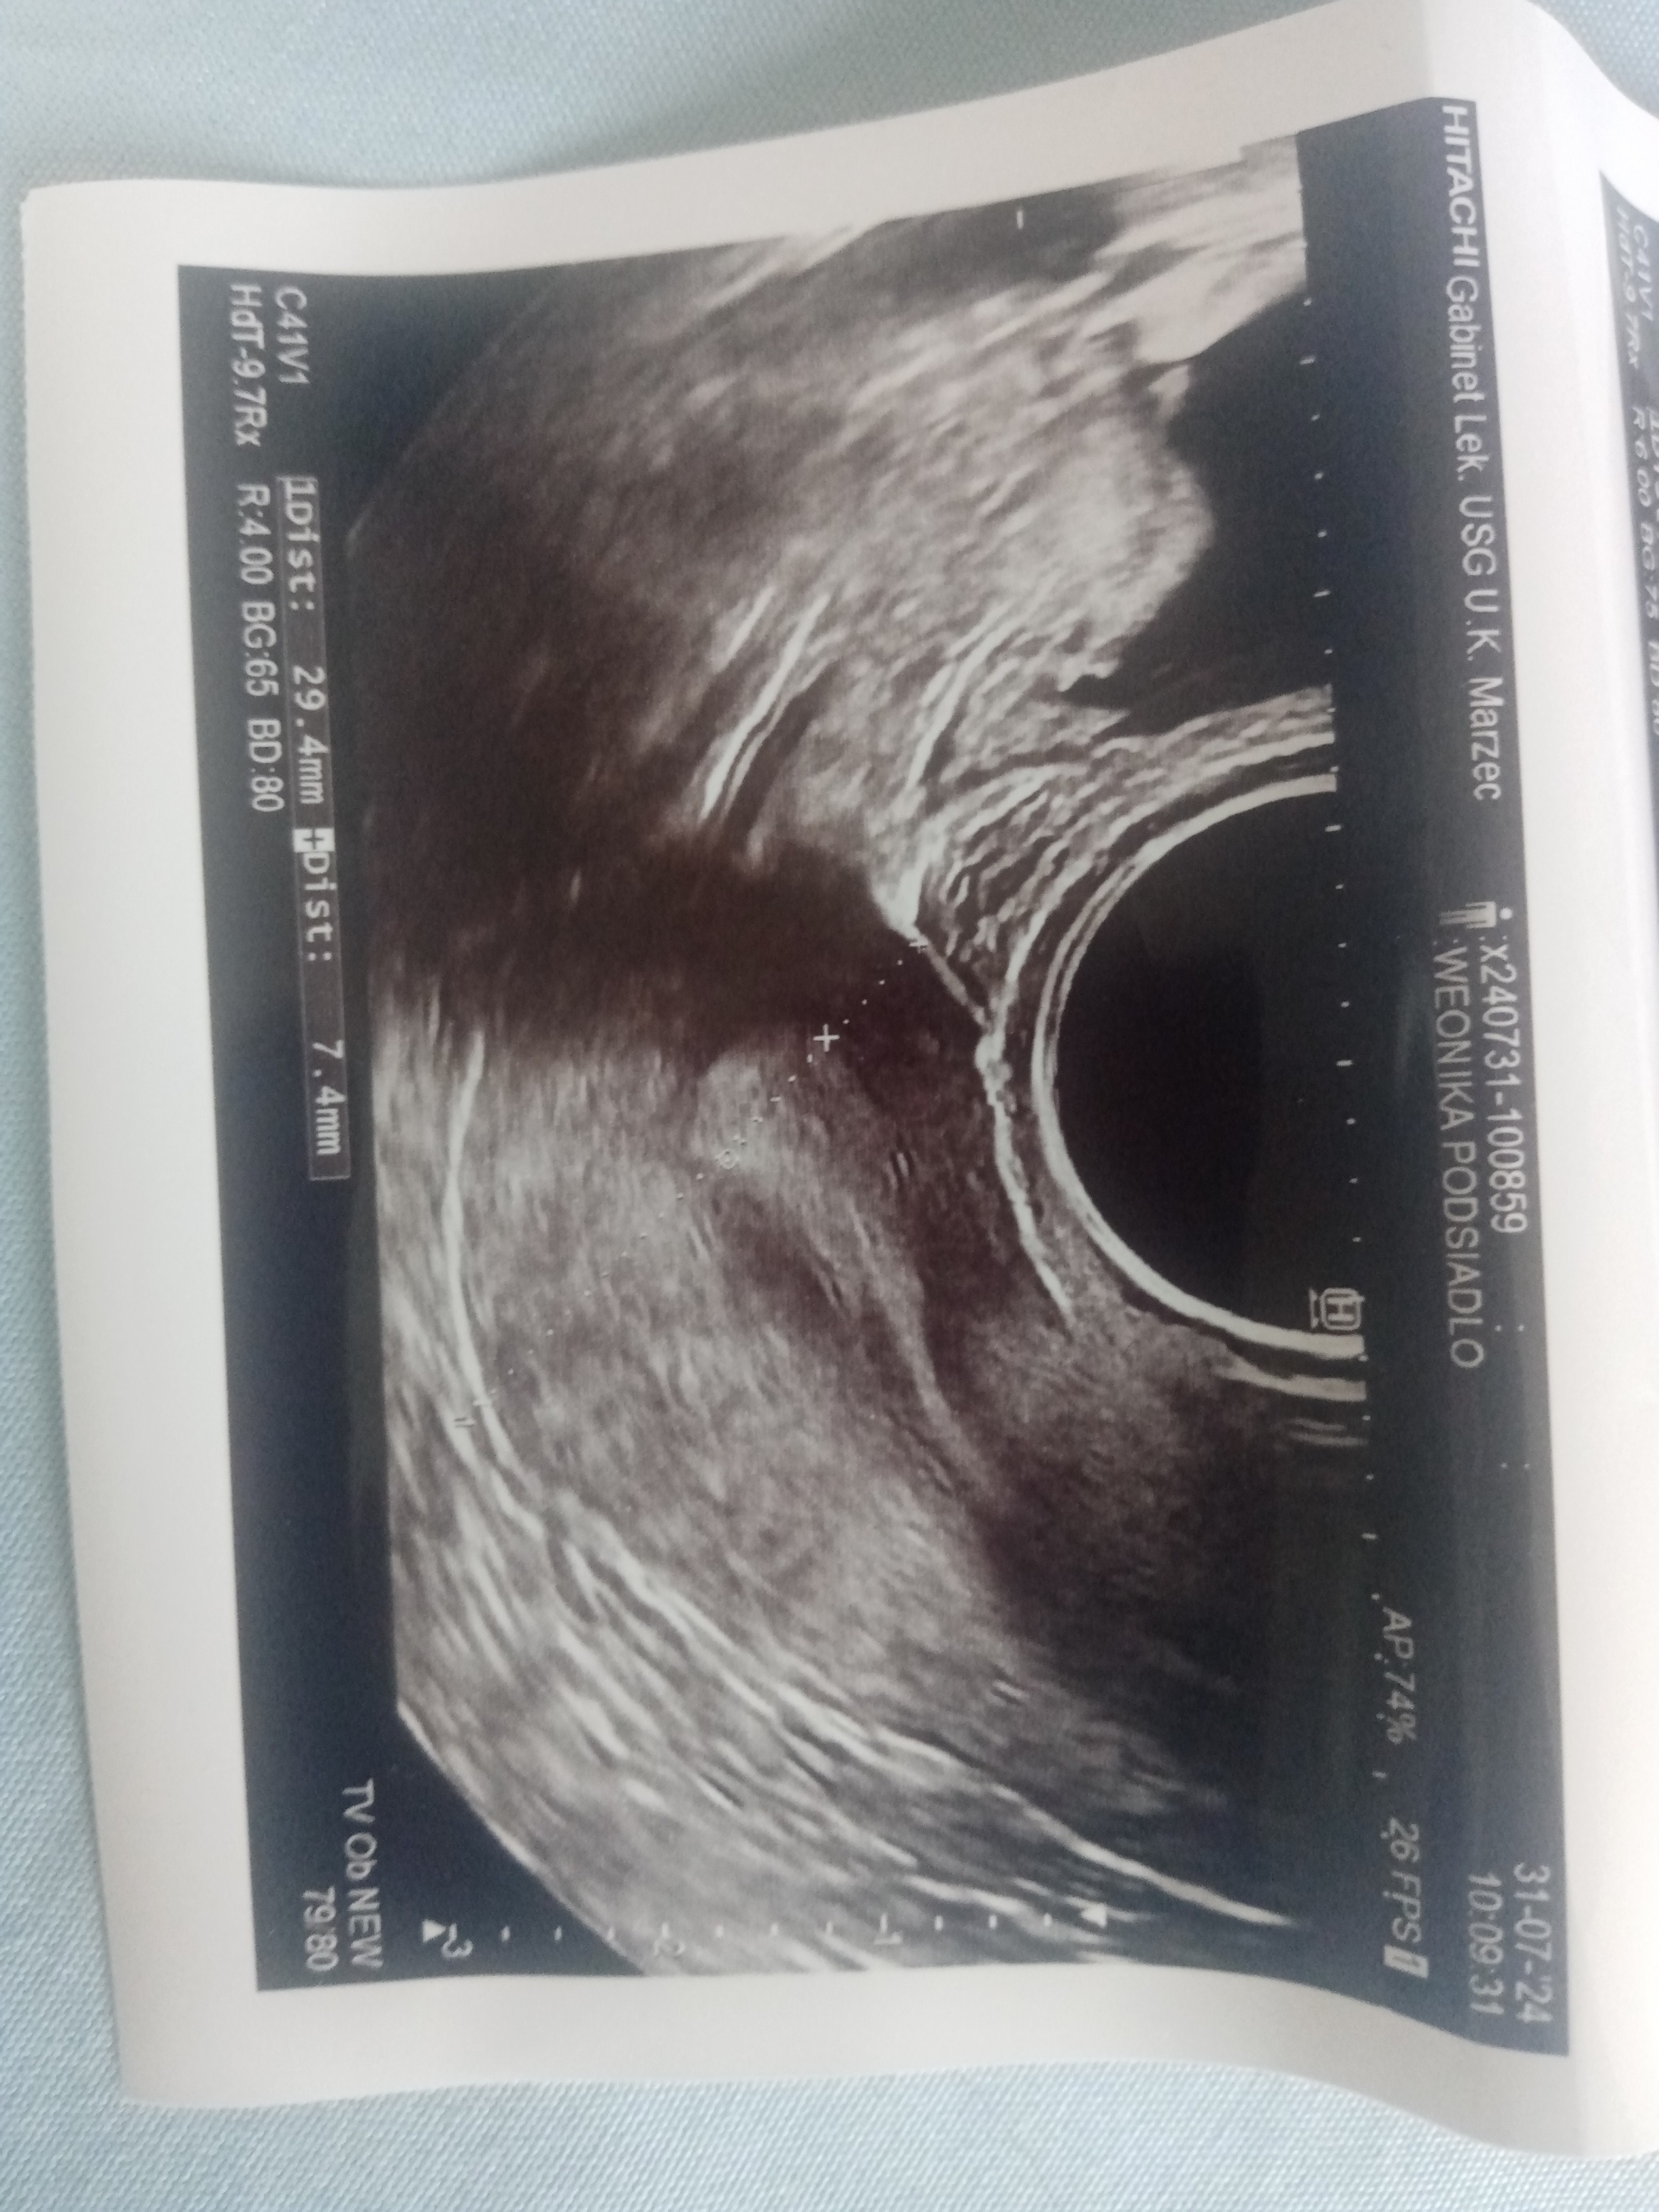

To moje usg narazie nic nie widać

Załączniki

• IMG_20240801_102044.jpg

IMG_20240801_102044.jpg

1,7 MB · Wyświetleń: 182